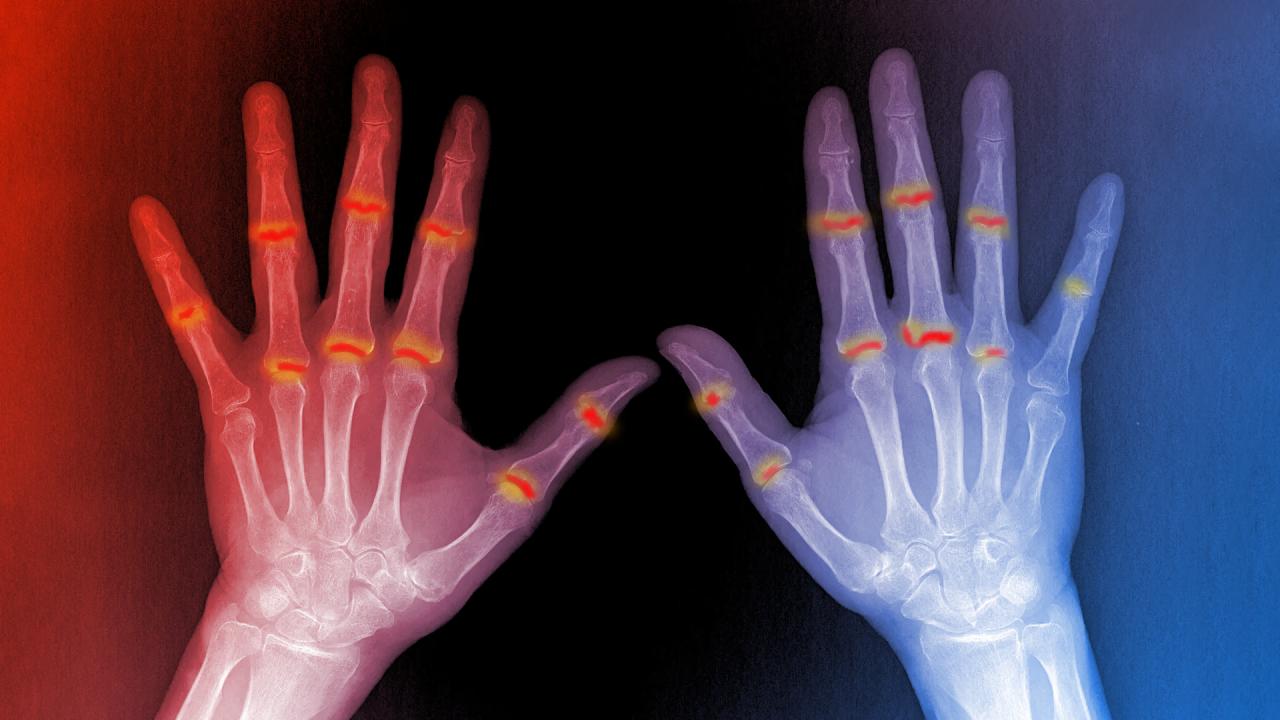

A pikkelysömör enyhe bőrtüneteiből akár súlyos ízületi bántalmak is kialakulhatnak, de eddig rejtély volt, hogy pontosan miért. Most kutatók feltárták a láncolatot, ami a bőrön kezdődik, és végül az ízületekben pusztítást okoz. Az immunsejtek – amelyek a gyulladt bőrterületeken képződnek – képesek a véráramba jutni egészen az ízületekig, ahol egyes esetekben komoly gyulladást indítanak el. Ennek felismerése esélyt ad arra, hogy a betegséget hamarabb diagnosztizálják, és megelőzzék az ízületek maradandó károsodását.

A vizsgálatok során kiderült, hogy a pikkelysömör nyomán képződő speciális immunsejtek nemcsak a bőrben maradnak, hanem a véráramba jutva eljuthatnak az ízületekhez is. Dr. Simon Rauber, a kutatócsoport vezetője kiemeli, hogy önmagában az immunsejtek jelenléte az ízületben nem elég a gyulladás elindításához – ehhez olyan körülmények is szükségesek, amelyek meggyengítik az ízület védekezését.

Az áttörést az a felismerés hozta, hogy a kötőszöveti sejtek – vagyis a fibroblasztok – jelentik az ízület belső védvonalát. Egészséges emberben ezek a sejtek megakadályozzák, hogy az immunsejtek gyulladást okozzanak. Ám azoknál, akiknél kialakul a pikkelysömörös ízületi gyulladás, ez a védelmi funkció jelentősen csökken. Így a gyulladást okozó sejtek akadálytalanul roncsolni kezdik az ízületet.

A legfontosabb újdonság, hogy ezek a veszélyes immunsejtek a vérben már azelőtt kimutathatók, mielőtt a páciensnél kialakulna az ízületi gyulladás. Ez lehetőséget teremt arra, hogy a magas kockázatú betegeket már egészen korán azonosítsák, és megfelelő kezeléssel megelőzzék a komoly ízületi károsodást. A jövőben talán célzott terápiákkal blokkolhatják majd ezeket a sejteket, mielőtt elérnék az ízületeket, és ezzel végleg búcsút lehetne inteni a pikkelysömörös ízületi gyulladásnak.